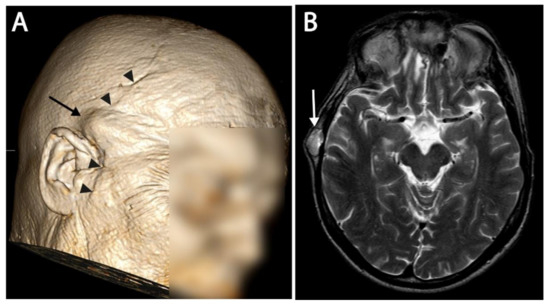

| Patient Number | Primary Tumour Location | Surgical Approaches | Postoperative Radiotherapy | Ectopic Recurrence Site | Time to First Ectopic Recurrence (Months) | Treatment of Recurrence |

|---|---|---|---|---|---|---|

| 3 | Craniocervical junction |

| Proton | Subcutaneous retroauricular Subcutaneous neck 3x Neck muscle left + right | 18 | Surgery Photon radiotherapy (Linac) |

| 4 | Clivus |

| Proton | Nose septum Subcutaneous nose | 147 | Surgery |

| 5 | Clivus |

| Proton / Photon | Ala minor os sphenoid Subcutaneous preauricular Frontal bone Subcutaneous frontal Dura mater frontal right | 41 | Surgery Photon radiotherapy (Linac) |

| Patient Number | Primary Tumour Dose (GyRBE) | Number of Fractions | Protocol | Regrowth of Primary Tumour after RT (Months) | Number of Ectopic Recurrences | First Ectopic Recurrence Area RT Dose (GyRBE) | Time Interval between Radiotherapy and First Ectopic Recurrence (Months) | Time Interval between First Surgery and RT (Months) |

|---|---|---|---|---|---|---|---|---|

| 1 | 74 | 37 | 54 GyRBE + 20 GyRBE boost | 9 | 4 | 54 | 9 | 5 |

| 2 | 78 | 39 | 56 GyRBE proton + 20 Gy photon boost | No regrowth of primary tumor | 2 | 1 | 22 | 18 |

| 3 | 74 | 41 | Standard skull base chordoma protocol | 37 | 5 | 50 | 24 | 24 |

| 4 | 74 | 37 | 54 GyRBE + 20 GyRBE boost | No regrowth of primary tumor | 2 | 1 | 98 | 23 |

| 5 | 68 | 34 | 48 GyRBE proton + 20 Gy photon Boost | No regrowth of primary tumor | 5 | 1 | 43 | 5 |

| Average | 74 | 37.6 | 39 | 3 | 21 | 41 | 17 |